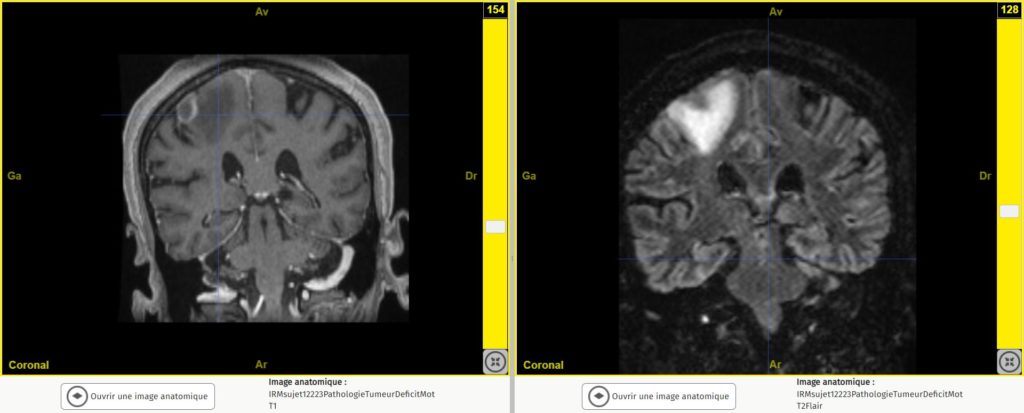

Si nous ouvrons et comparons ces 2 images que constatons-nous.

Sur l’image de gauche (T1) la substance blanche apparaît plus claire que le cortex, alors que sur l’image de droite (T2) c’est le contraire.

Le sujet 12223 est atteint d’une tumeur à l’origine d’un déficit moteur. Cette tumeur apparaît bien plus nettement en T2 (à droite) qu’en T1 (à gauche).